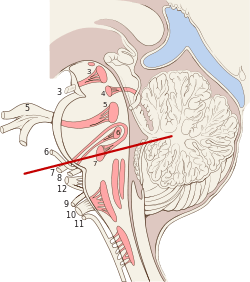

Scheme showing central connections of the optic nerves and optic tracts. Brain stem sagittal section

Brain stem sagittal section